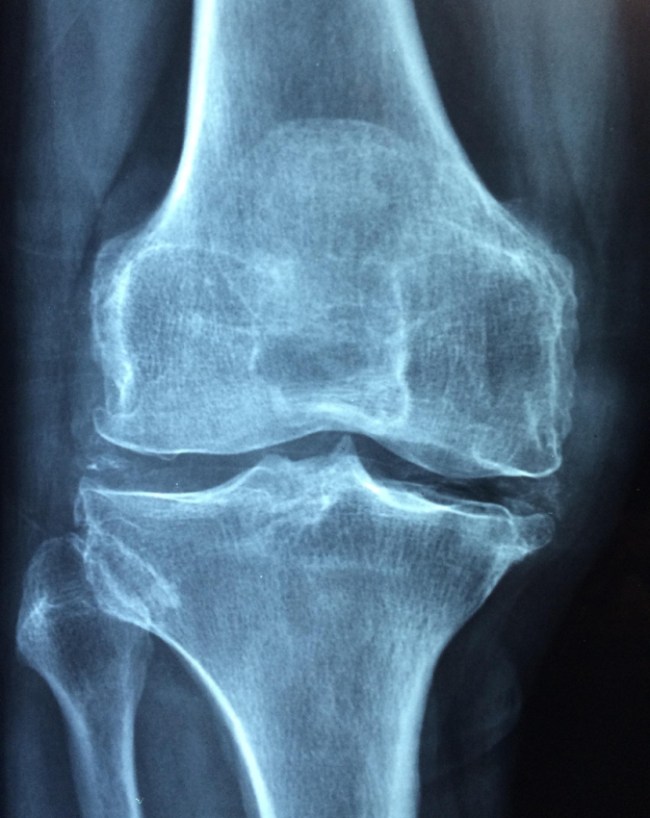

आपने गौर किया होगा कि उम्र बढ़ने के साथ-साथ हड्डियां कमजोर होने लगती हैं, जिस कारण हल्की चोट में लंबे समय तक दर्द, फ्रैक्चर, आदि का खतरा बढ़ जाता है. हम आपको इस स्टोरी में इसके कारण और राहत पाने के उपाय बताएंगे.

40 के बाद हड्डियों के कमजोर होने की समस्या आज के वक्त में इतनी आम चली है कि बड़ी संख्या में लोग दर्द, सूजन आदि तरह-तरह की समस्या लेकर आते रहते हैं. उम्र बढ़ने के साथ शरीर में कैल्शियम का अवशोषण कम हो जाता है और बोन डेंसिटी घटने लगती है. महिलाओं में मेनोपॉज के बाद यह प्रक्रिया और तेज हो जाती है.